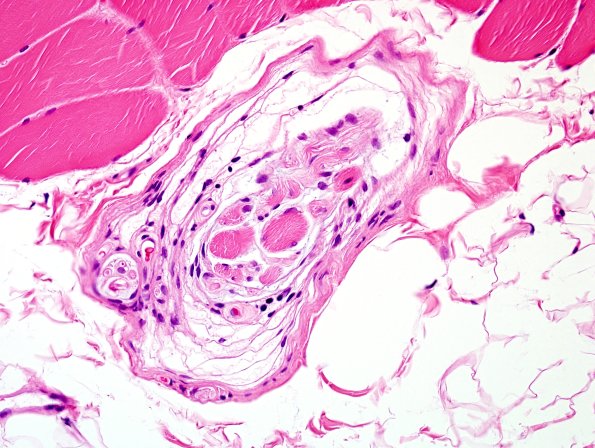

Muscle Spindle

Two muscle spindles showing the capsule separating intrafusal muscle fibers from adjacent extrafusal fibers. (H&E)